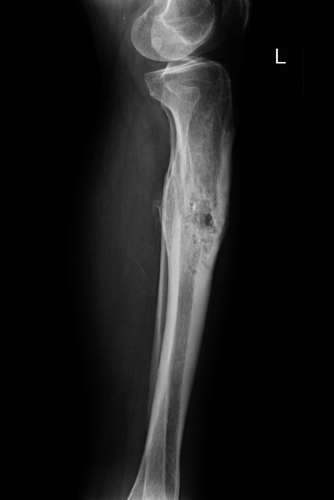

Osteomielite nei bambini: le infezioni da non sottovalutare

È un’infezione dell’osso e della cavità midollare. Diagnosi rapida e cure tempestive limitano gli effetti della malattia

L’osteomielite è un’infezione dell’osso e della relativa cavità midollare. Rientra nelle infezioni osteoarticolari che colpiscono sempre di più i bambini di tutto il mondo.

Può interessare qualsiasi osso, ma il femore, la tibia, l’omero e il calcagno sono le localizzazioni più frequenti. Per ridurre al minimo le conseguenze permanenti della malattia sono indispensabili una diagnosi tempestiva e un trattamento adeguato.

• Radiografia tradizionale: permette di distinguere fratture o processi tumorali